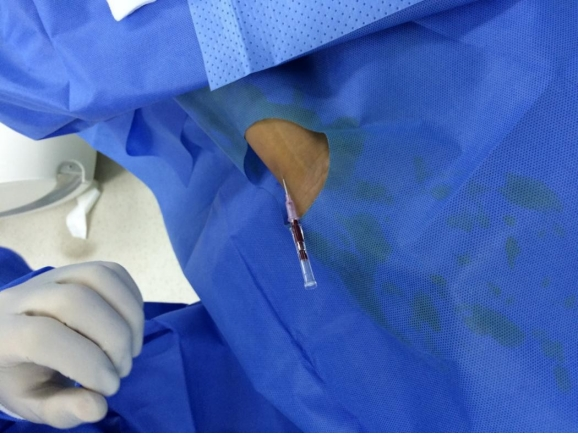

穿刺:

操作者右手持注射器,左手食指和中指轻触受试者右桡侧探明桡动脉路线,于右桡侧第二掌横纹下1.5cm左右搏动较强处垂直刺破皮肤,再调整针尖角度为30-40°沿左手食指搏动最强处前向刺入,直至穿刺针尾部冒血。

置鞘:

右手稳住针鞘,左手缓慢退出穿刺针;待针鞘向外喷血,左手稳住针鞘,右手持导丝从尾部放入针鞘,直至2/3进入体内;左手按住穿刺点,右手捏住针鞘缓慢退出体内,保留导丝;用扩皮刀在穿刺点口轻轻向上挑开皮肤完成扩皮;右手持肝素盐水冲洗过的已组装好的桡动脉鞘管,通过导丝并在左右旋转下进入桡动脉,直至合适长度;左手稳住桡动脉鞘管,右手将导丝连同鞘芯一起退出体外。

两点法:两个桡A搏动点以明确血管走行;穿刺点:桡骨茎突近心端水平;角度:30度左右;穿刺法:穿透法比喷血法好;少用局麻:皮下,少于0.5ml利多;预防痉挛:硝酸甘油200μg鞘内注射;穿透法喷血后左手扶针鞘,缓慢退鞘,手一定要稳;导丝进入困难时建议导丝塑弯透视下调整。